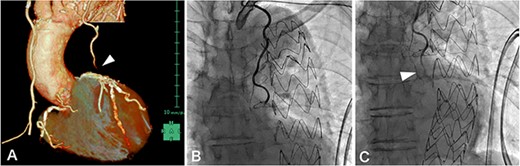

MIDCAB, harvesting of a pedicled LITA followed by an end-to-side anastomosis to the LAD with a sufficient intraoperative graft flow, was performed through left anterior mini-thoracotomy. Although the patient’s chest symptoms were vague and serum cardiac biomarkers were not elevated postoperatively, routine contrast-enhanced multi-slice CT (MSCT) on postoperative Day 3 suggested the middle of LITA graft occlusion (Fig. 1A). The following CAG also demonstrated thrombotic occlusion (Fig. 1B and C). Subsequently, we performed PCI for the lesion in the LITA graft. The lesion was crossed with a 0.014-inch guidewire (SION Blue, Asahi Intecc, Aichi, Japan); afterward, balloon dilation (Ryurei 2.0 × 20 mm, Terumo, Tokyo, Japan) was performed repeatedly. Three stents (Synergy 2.25 × 12 mm, 2.25 × 28 mm, 2.25 × 20 mm; Boston Scientific, USA) were overlappingly placed to cover the lesion, and a satisfactory angiographic result was observed (Fig. 2). The patient had an unremarkable hospital stay and remained symptom-free 2 years postoperatively.

A 0.014-inch guidewire (SION Blue, Asahi Intecc, Aichi, Japan) was inserted into the LITA graft under intravascular ultrasound (Altaview; Terumo, Tokyo, Japan) guidewire; the diameter of the lesion was about 2 mm, therefore balloon dilation (Ryurei 2.0 × 20 mm, Terumo, Tokyo, Japan) was performed first from distal to proximal (A); angiography showing hematoma formation in the lesion, which was not resolved by the administration of nitroglycerin (B, arrowhead); three stents (Synergy 2.25 × 12 mm, 2.25 × 28 mm, 2.25 × 20 mm, Boston Scientific, USA) were overlappingly placed to cover the lesion (C, dotted line), and there was a satisfactory angiographic result.